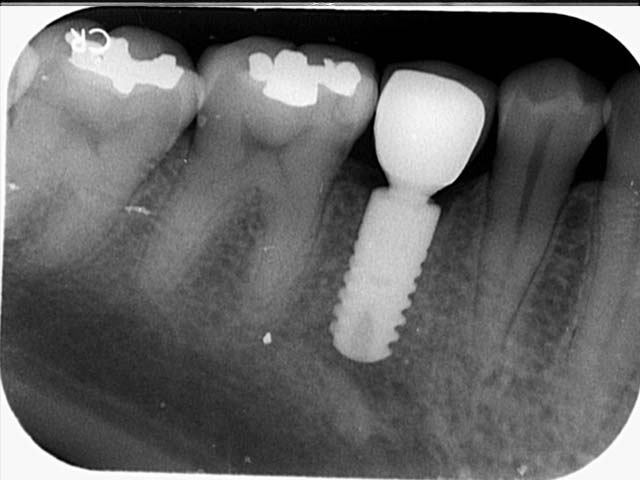

斷裂蛀蝕牙根

拔牙+植牙